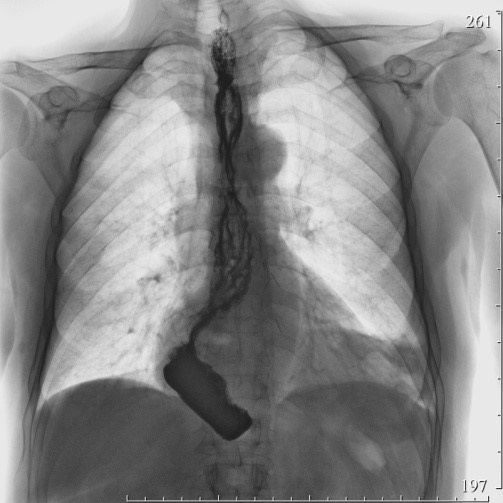

2174. Больному, оперированному ранее по поводу ахалазии кардии 4 стадии, выполнена эзофагопластика желудочной трубкой, в настоящий момент при КТ (компьютерная томограмма) органов грудной клетки определяется